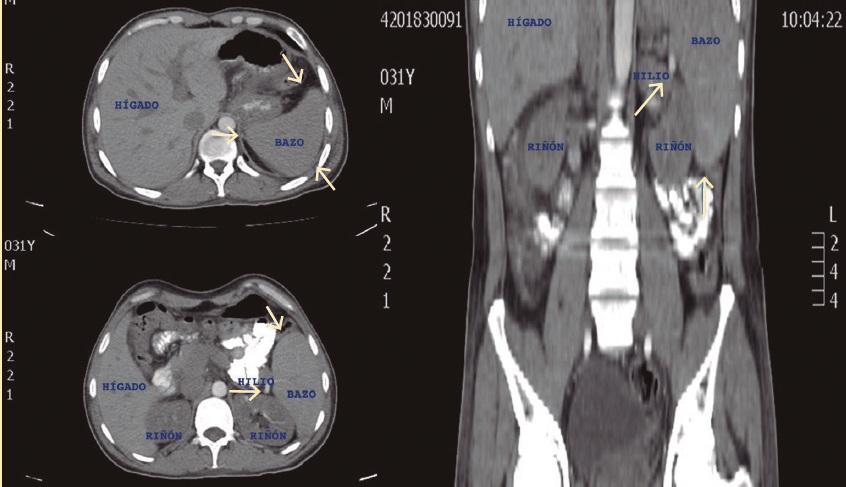

Fue enviado a la consulta externa del servicio de cirugía general por falla en el tratamiento médico. Como parte del protocolo preoperatorio, se solicitaron ultrasonido abdominal (figura 1) y tomografía axial computada (figura 2) para determinar las características anatómicas de bazo, además de estudios de laboratorio, se reportó una cifra preoperatoria de plaquetas de 27,000/mm3. Se decidió intervención quirúrgica de forma programada con plan de esplenectomía laparoscópica. Se solicitó valoración por el servicio de infectología para la aplicación de vacunas contra bacterias encapsuladas, las cuales fueron aplicadas 48 horas posteriores a la cirugía.

Imágenes: otorgadas por los autores

Figura 2 Tomografía axial computada de paciente con PTI que demuestra aumento en los ejes mayores del bazo (flecha).